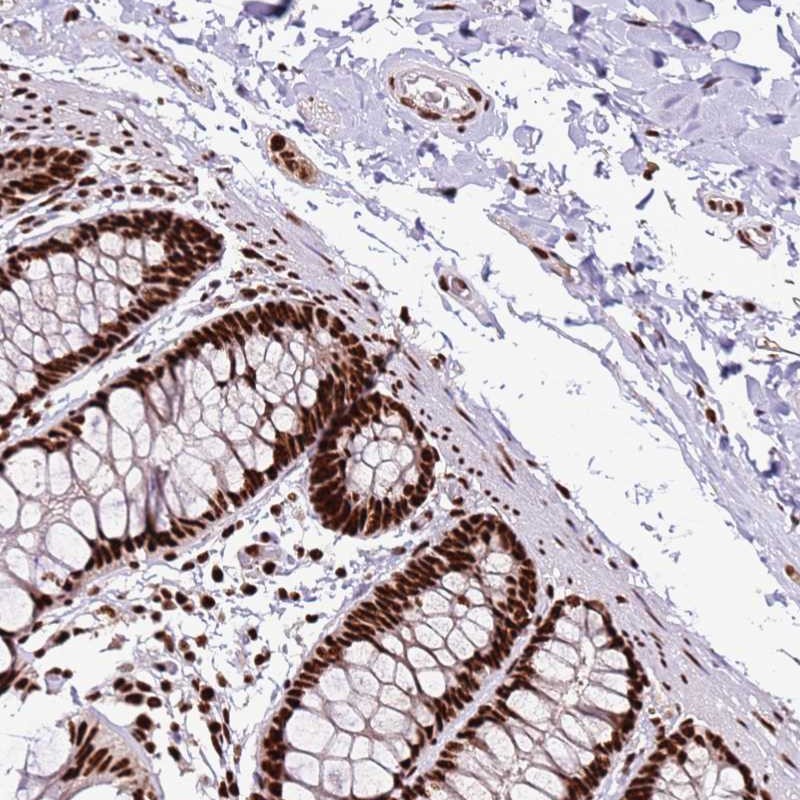

Immunohistochemical staining of human colon shows strong nuclear positivity in glandular cells and ganglion.